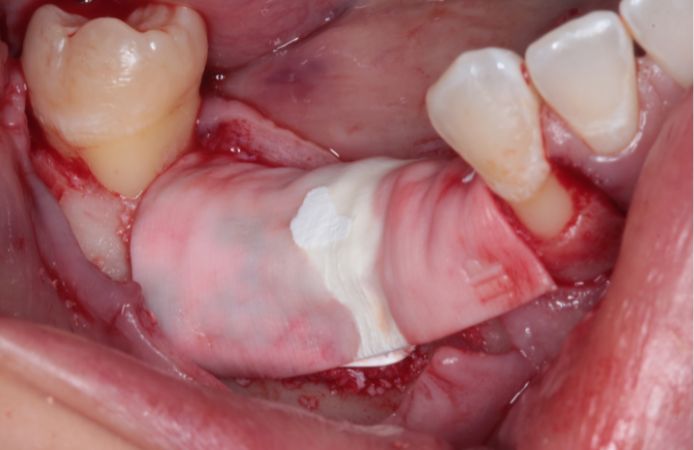

Figure 11.

Re-entry nine months after augmentation, after removal of the membrane. Note the level and width of regenerated bone. The newly formed bone is highly vascularized as indicated by abundant bleeding during site preparation for implant placement.